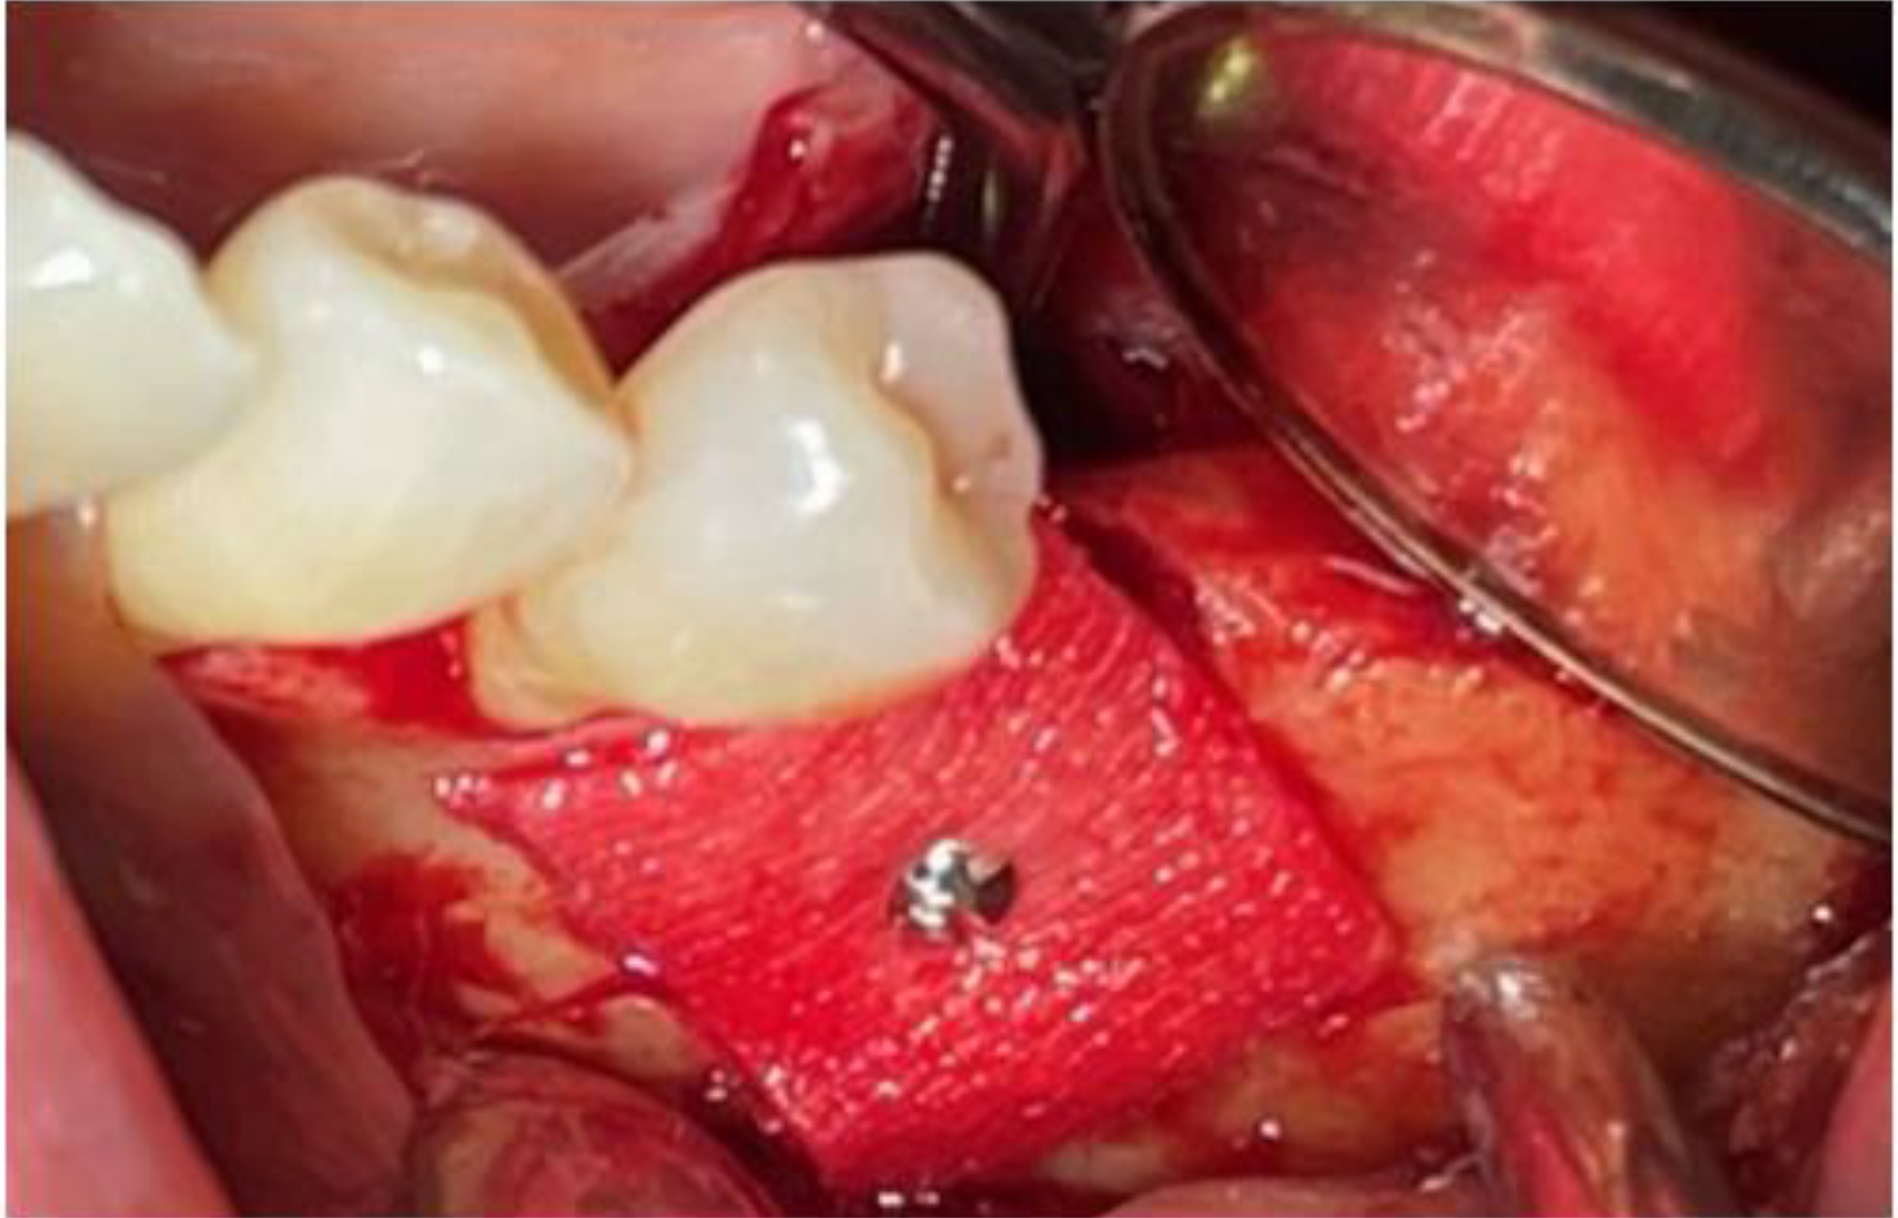

During surgery, the dehydrated ADM was carefully cut and folded to achieve a total thickness of approximately 0.6–1.2 mm. It was then immersed in 0.25 mg of rhBMP-2 dissolved in 0.5 mL of normal saline for 1 min. The prepared ADM was applied to the buccal bone defect and a titanium fixation screw was used to stabilize the graft material in position (Fig. 5). The surgical site was then carefully closed using simple interrupted sutures.

CBCT analysis performed 5 months postoperatively confirmed a horizontal bone gain of approximately 1.7 mm. Newly formed bone with homogeneous density and continuity was observed around the implant (Fig. 6). Throughout the 10-month functional loading period, no signs of inflammation, bone resorption, or other complications were observed in the surrounding hard or soft tissues. The implant remained functionally stable.